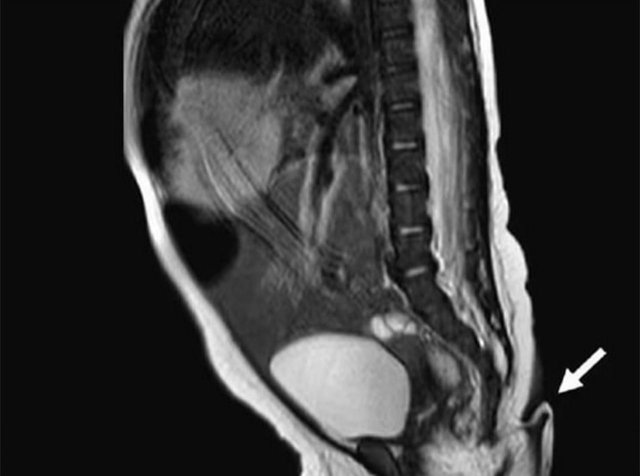

В Мексике девочка родилась с шестисантиметровым хвостом (2 фото)

Врачи смогли удалить аномалию, но были в шоке, потому что это первый подобный случай в стране. Сообщается, что в хвосте были не только мягкие ткани, но и артерии, вены, а также пучки нервов. С самой малышкой все хорошо - она доношена, а беременность прошла без осложнений. Говорят, что такой отросток может возникнуть из-за опухоли.